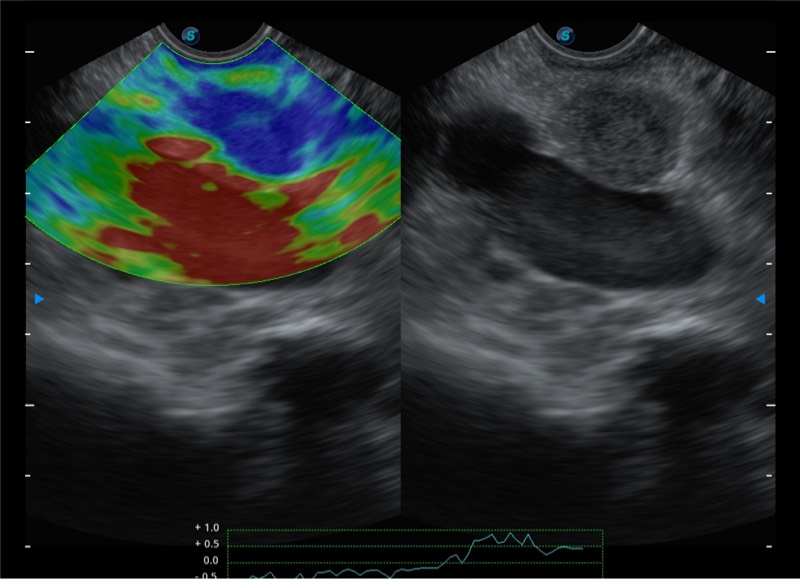

搭载百万级CMOS成像技术

及自主研发凸阵换能器,

可呈现优质的内镜和超声画面

基于二十年的超声技术积累,开立提供了最新一代的独立超声主机,在提供高质量图像的同时满足多学科使用。具备常见多普勒技术并提供弹性成像、声学造影等高端影像技术。新一代传感器具有更强的抗干扰能力并减少图像伪影。

150°超声扫描角度

4-12MHZ宽频输出